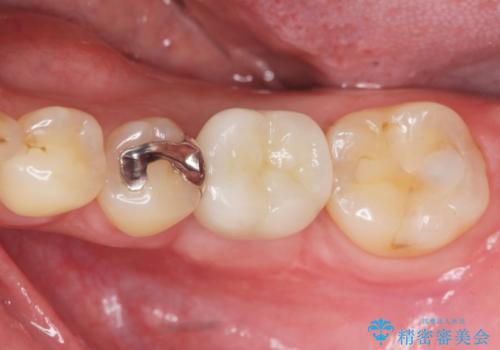

- 銀歯の奥歯で噛むと違和感・痛みがあるとのことで検査・治療を求めて来院されました。

銀歯を除去して見ると内部で虫歯が再発し、歯の辺縁は破折し保存が難しく抜歯をしなければいけない状態でした。

抜歯後ブリッジとインプラント治療を検討・相談し、より周囲の歯を削らずに済むインプラント治療を希望されたのでインプラントによる機能回復を計画します。